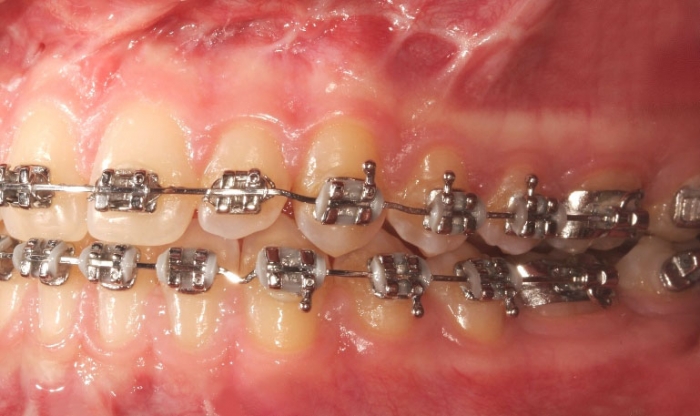

Mordida inicial - Clínica Cliniface

Mordida inicial